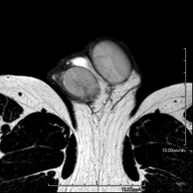

Prova diagnòstica no invasiva que consisteix en l'obtenció d'imatges d'alta definició anatòmica de les articulacions temporo-mandibulars mitjançant l'ús d'un camp electromagnètic i ones de ràdio (amb un emissor i un receptor). No utilitza radiació ionitzant. Es realitza un estudi funcional de les ATM, en les diferents fases d'obertura i tancament de la boca. Indicacions: dolor, bloqueig de l'articulació i sorolls en mastegar. - RM d'Òrbites